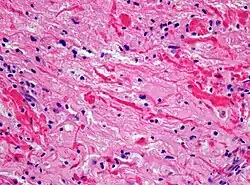

| Micrograph of a pilocytic astrocytoma, showing characteristic bipolar cells with long pilocytic (hair-like) processes. Smear preparation. H&E stain. | |

Under the microscope, the tumor is seen to be composed of bipolar cells with long "hair-like" GFAP-positive processes, giving the designation "pilocytic" (that is, made up of cells that look like fibers when viewed under a microscope[6]). Some pilocytic astrocytomas may be more fibrillary and dense in composition. The presence of Rosenthal fibers,[7] eosinophilic granular bodies, and microcysts can often be seen. Myxoid foci and oligodendroglioma-like cells may also be present, though these are not specific to pilocytic astrocytoma. Long-standing lesions may show hemosiderin-laden macrophages and calcifications.

Histopathology of pilocytic astrocytoma (grade I WHO). H&E stain. Original magnification 200x.

Histopathology of pilocytic astrocytoma (grade I WHO). H&E stain. Original magnification 200x. -

Histopathology of Rosenthal-fibres. H&E staining showing these elongated eosinophilic structures in the case of pilocytic astrocytoma. Magnification 400x

Histopathology of Rosenthal-fibres. H&E staining showing these elongated eosinophilic structures in the case of pilocytic astrocytoma. Magnification 400x